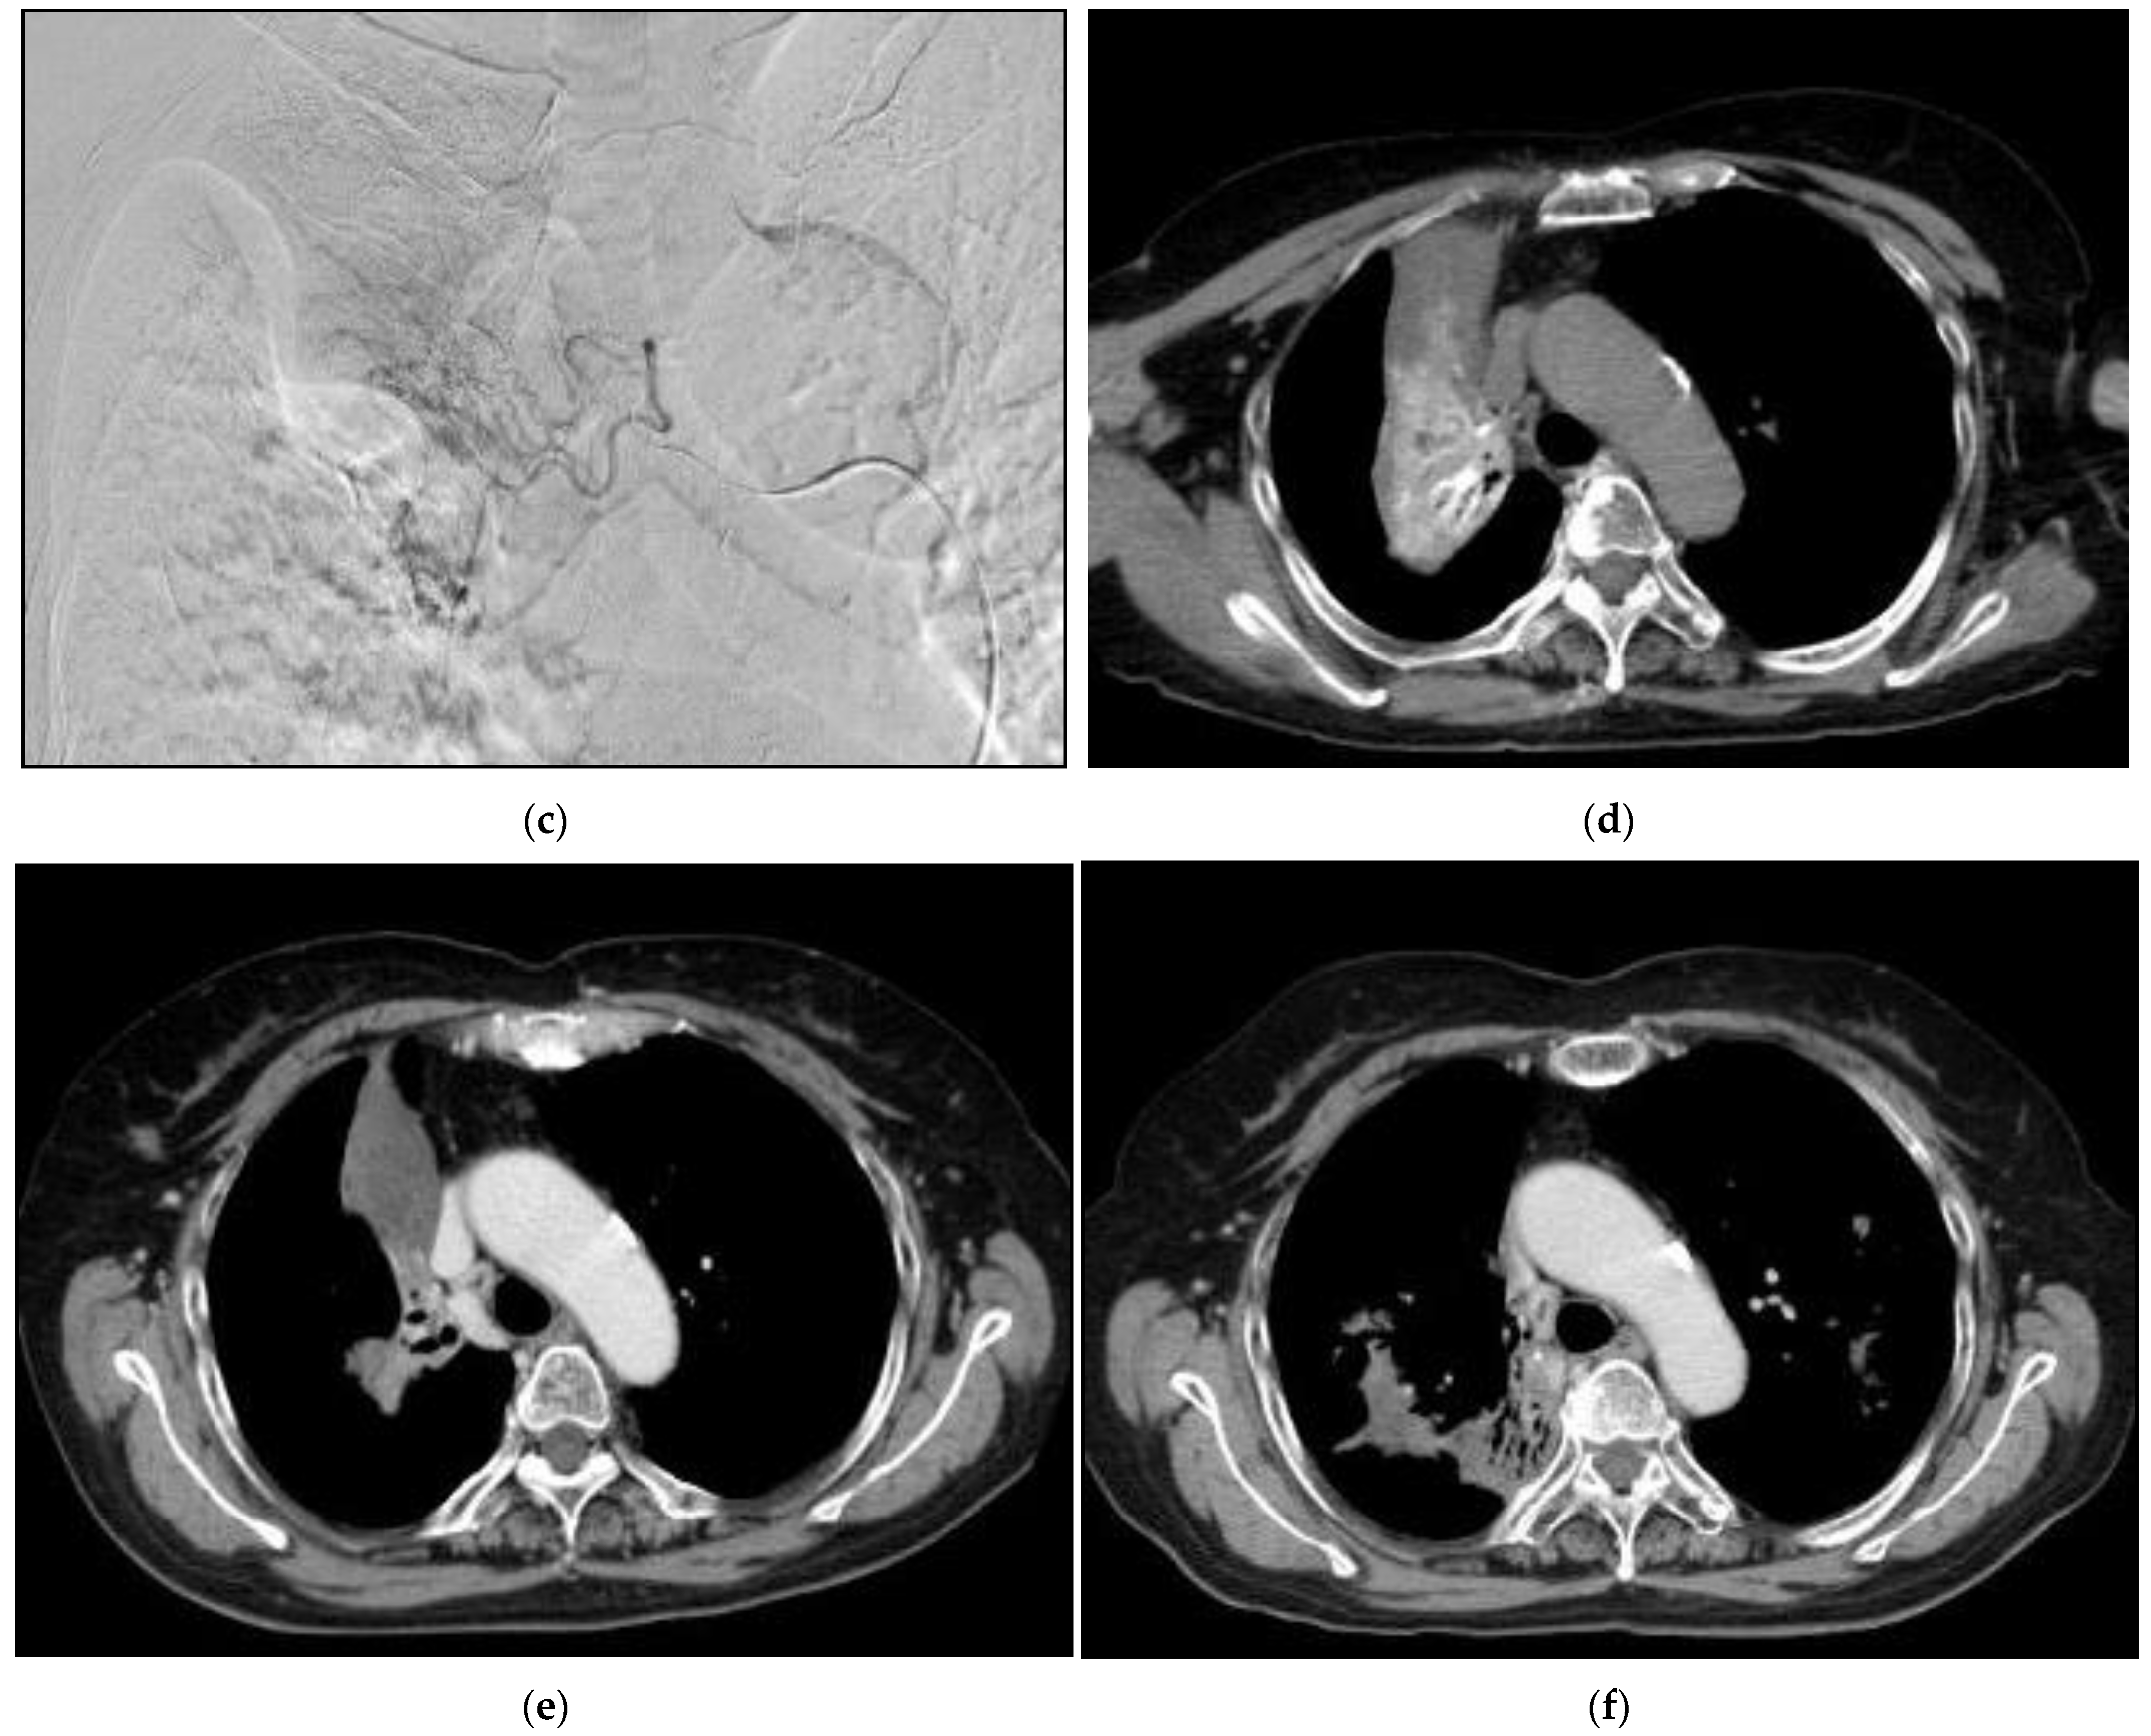

Case 1: A 67-year-old man consulted our clinic with a local recurrence of lung cancer in the left pulmonary hilum (Figure 10). He had got systemic chemotherapy and radiotherapy. Symptoms at consultation were severe cough and respiratory distress. The first treatment through the bronchial arteries was carried out by infusing 5-FU; 250 mg, CDDP; 20 mg, DOC; 20 mg, BV; 200 mg with embolization by 3.0 mg of HepaSphere (50–100 micron). In total, 8 sessions of treatment have been repeated. The patient at present (April 2022) has no clinical symptoms except for a slight cough with no clinical problems in the activity of daily life (ADL).

Figure 10. Recurrent adenocarcinoma in the lung. 67-years-old man. (a): Contrast-enhanced CT A tumor in the left upper lobe invading mediastinum with mediastinal lymph node metastases. The longitudinal diameter was 67 mm. (b): A volume rendering 3D image of the aorta and its’ branches. The main left bronchial artery (arrow) was clearly shown to arise from the anterior wall of the descending aorta. (c): Selective DSA (Digital Subtraction Angiography) of the left main bronchial artery. It was difficult to assess the tumor supply from the bronchial arteriography. (d): Angio-CT of the bronchial artery. The blood supply to the whole tumor was recognized by infusion of contrast into the left bronchial artery. (e): A contrast-enhanced in a month after the initial therapy. Tumor reduction was observed. The diameter was 50 mm. (f): A contrast-enhanced CT in one year after the initial therapy. The diameter was 51 mm. Six sessions of treatment were carried out in one year. (g) A contrast-enhanced CT in 20 months after the initial therapy. The diameter was 56 mm. Eight sessions of treatment were carried out in the clinical course.